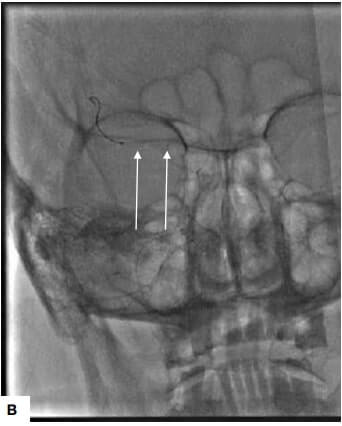

The DSA image demonstrated right M1 occlusion. A mechanical thrombectomy procedure was performed for the patient. Post thrombectomy, there was recanalization of the left MCA and its branches. The patient showed on table improvement in the power of the left upper and lower limb. He had immediate post-procedure improvement of left upper and lower limb weakness